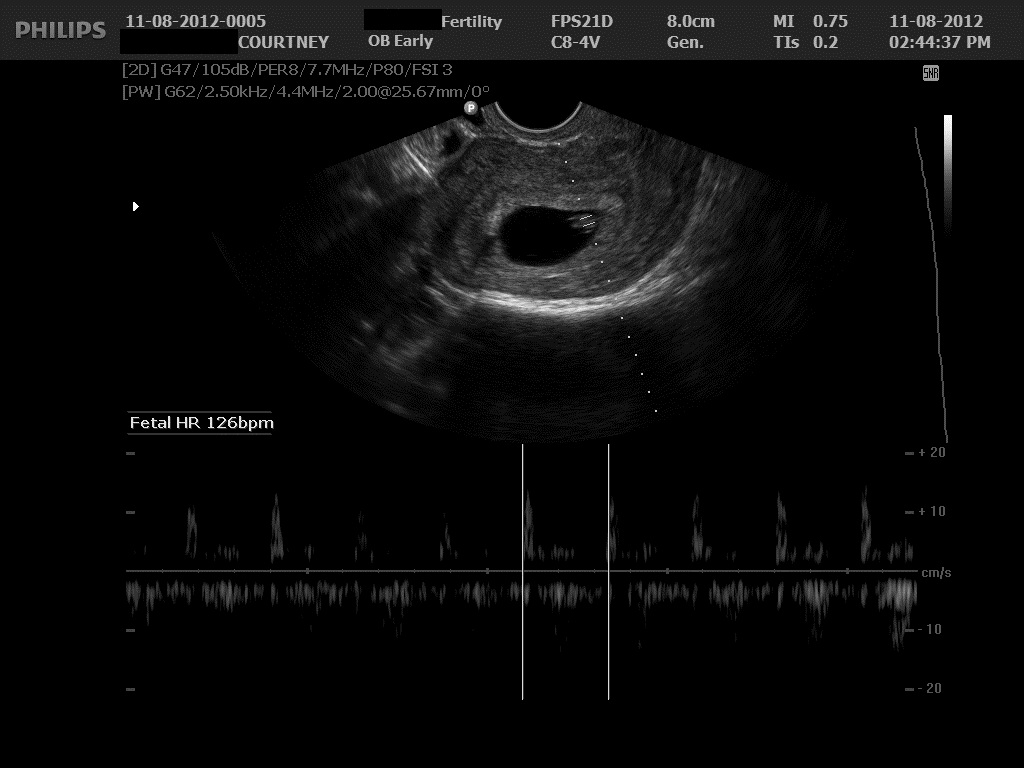

Ultrasound 1 November 12, 2012 by Courtney Leave a comment ← Previous Image Next Image → 6w4d – Heartbeat of 126 bpm Like Loading...